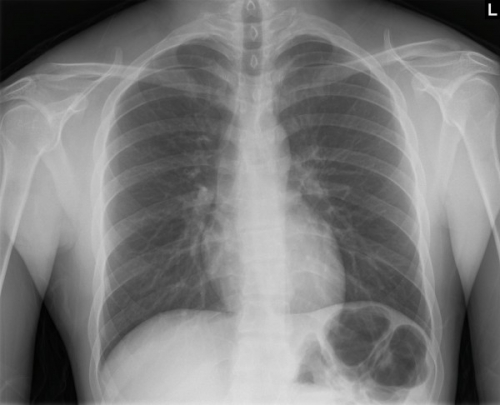

Tool to train medical student's eyes as to what a normal chest x-ray looks like, with over 500 consecutive normal images.